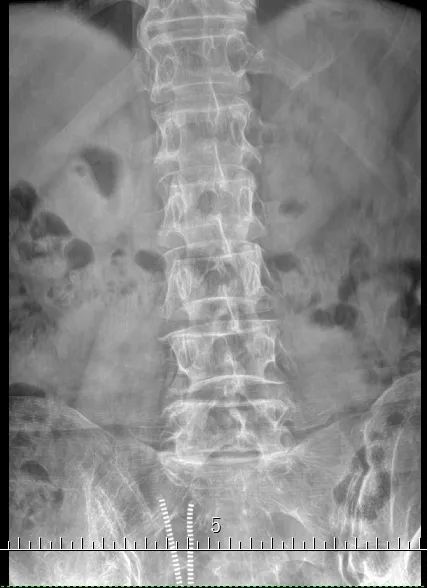

术前的磁共振及X光片

今天要给大家介绍的是82岁的盛老伯。孝顺镇某村人。时不时有腰痛不适的感觉已多年。近3多个月来,腰痛逐渐加重,并出现左下肢的麻木和疼痛,走路不方便,稍走远一点,左下肢就疼痛难忍,需要歇一会才能继续行走。为了减轻疼痛,必须弯腰走路。曾经用过许多药物及针灸治疗,但是不见好转。十多天前到仁康医院就诊,拍片及磁共振检查发现腰椎第四、第五节之间明显骨质增生,同时有椎间盘突出,椎管狭窄。由于神经压迫明显,只能通过手术,取除突出的椎间盘,扩大狭窄的椎管,才能解除症状。